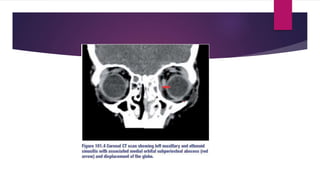

 CT scan is the initial radiologic investigation of choice

 Compared to AFRS, invasive FRS tends to have more focal bony erosions, lacks expansion of

the sinuses, has more limited sinus disease and has more disease outside of the sinuses than

within when there is intra-orbital or intra-cranial extension.

 Contrast enhanced computed tomography (CT) is advised as first-line imaging

because of its superiority in demonstrating bony anatomy and pathology of the

orbit and sinuses with its speed and ease of examination.

 3. Subperiosteal abscess – CT scans show a typical lenticular rim-enhancing collection adjacent

to the lamina papyracea with a fat plane between it and the displaced medial rectus muscle

 Lateral deviation and proptosis of the globe may be visible on axial images.

 Sight threatening complications of optic neuritis or optic nerve ischemia may also be present

without radiological signs. Subperiosteal abscess secondary to frontal sinusitis typically forms an

abscess superiorly with anteroinferior globe displacement